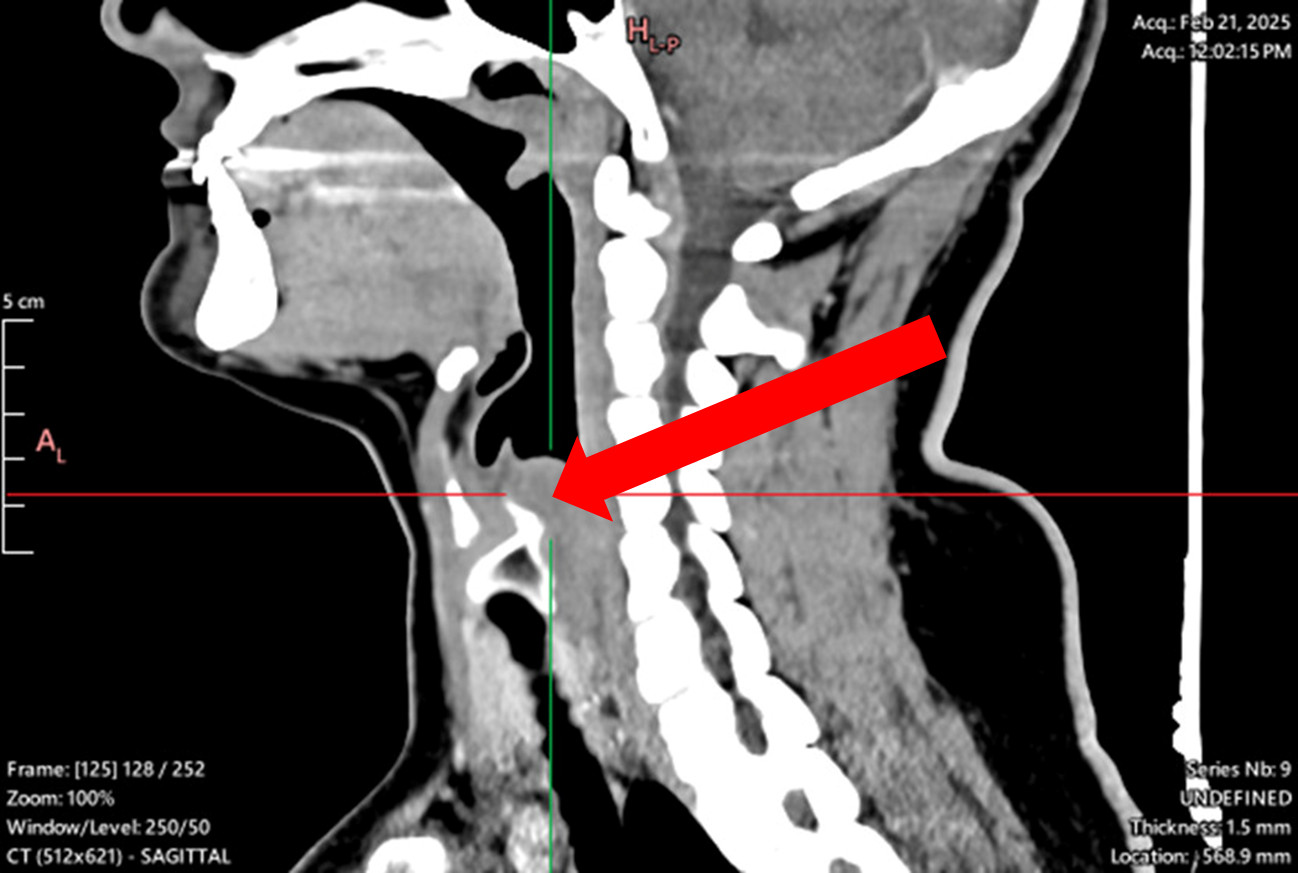

Abrikossoff tumor in postcricoid region

Preoperative image